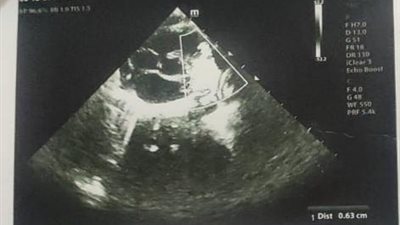

توصلت دراسة حديثة إلى أن العزلة الاجتماعية يمكن أن تؤدي إلى خطر الإصابة بالنوبات القلبية والسكتات الدماغية، حيث توصل الباحثون إلى أن الوحدة والعزلة أحد عوامل الخطر التي تؤدي إلى الإصابة بأمراض القلب التاجية والسكتات الدماغية، وأن للعلاقات الاجتماعية صلة وثيقة بصحة القلب والأوعية الدموية.

وأكد الباحثون، مدى ارتباط صحة القلب والأوعية الدموية بالعزلة الاجتماعية، حيث أن الوحدة ترتبط بنسبة 29% بالنوبات القلبية، وبنسبة 32% بالسكتات الدماغية، كما أن الاضطرابات النفسية والتغيرات المزاجية الناتجة عن العزلة النفسية مثل القلق والإجهاد الوظيفي، يمكن أن تؤدي إلى الوفاة المبكرة نتيجة التعرض لنوبات القلب أو السكتات الدماغية.